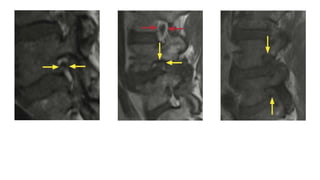

Spinal Canal Stenosis With Redundant

Nerve Roots at L3 to L4 as a result of

anterolisthesis due to facet joint

(concentric spinal canal stenosis with

hypertrophy of the ligamenta flava and disc

bulging, redundant nerve roots of the cauda

equina

Redundant Nerve Roots. T2 weighted (A) and magnetic

resonance (MR) myelography (B) images. Postoperative status

after laminectomy at L2 to L3 for a spinal canal stenosis.

Sagittal T2 weighted image and the myelo-MR shows residual

redundant nerve roots of the cauda equina proximal to the

previous spinal canal stenosis.

• With high-gradestenosis in the lumbar spine, the nerve roots proximal to the spinal canal stenosis can be elongated, large and tortuous; this phenomenon is called ‘redundant nerve roots’ . Spinal Canal Stenosis With Redundant Nerve Roots at L3 to L4 as a result of anterolisthesis due to facet joint (concentric spinal canal stenosis with hypertrophy of the ligamenta flava and disc bulging, redundant nerve roots of the cauda equina

• 68.

Redundant Nerve Roots.T2 weighted (A) and magnetic resonance (MR) myelography (B) images. Postoperative status after laminectomy at L2 to L3 for a spinal canal stenosis. Sagittal T2 weighted image and the myelo-MR shows residual redundant nerve roots of the cauda equina proximal to the previous spinal canal stenosis.